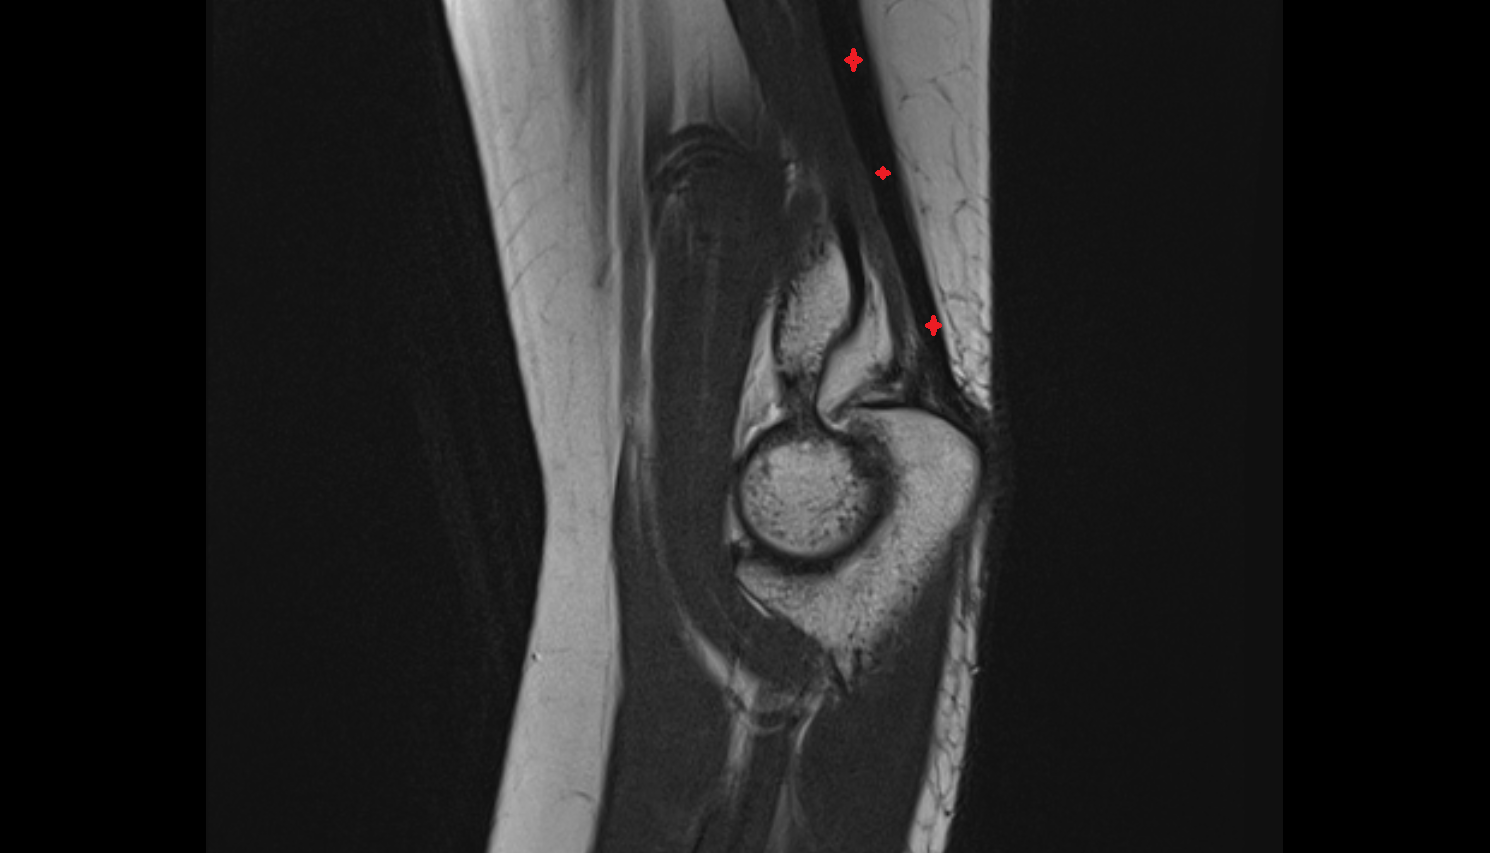

- Anterior cruciate ligament

- Posterior cruciate ligament